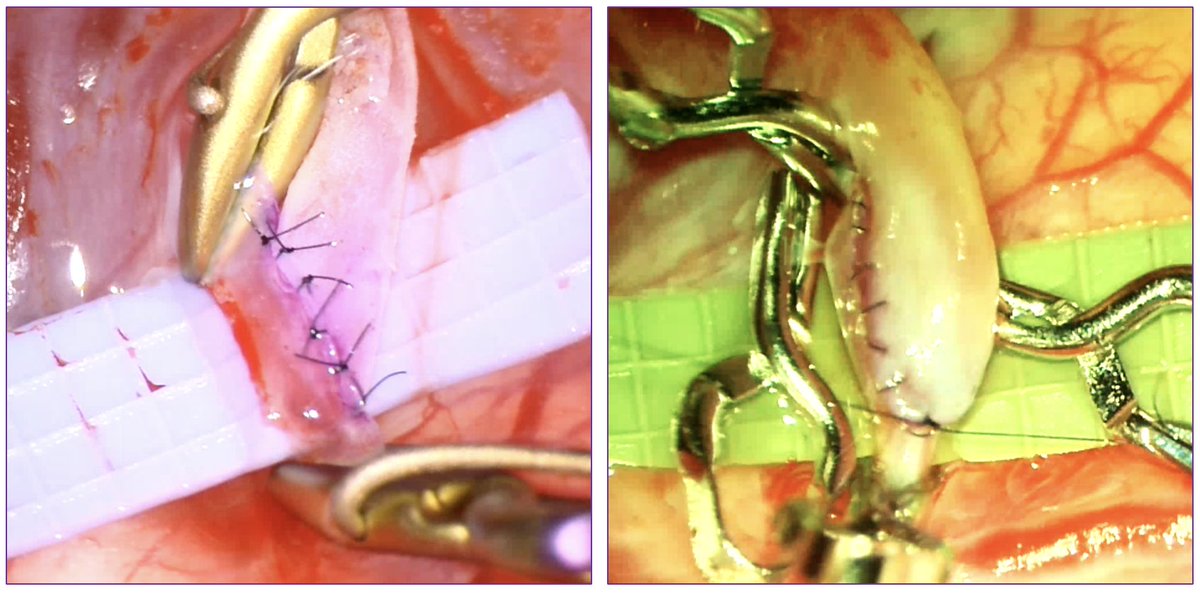

Finally! Running vs. Interrupted sutures in STA-MCA cranial bypass. We have assessed and compared long term angiographic results. No differences in patency or in STA caliber. Better results for the Running group when comparing anastomosis growth! @nyulangone @NYUneurosurgery